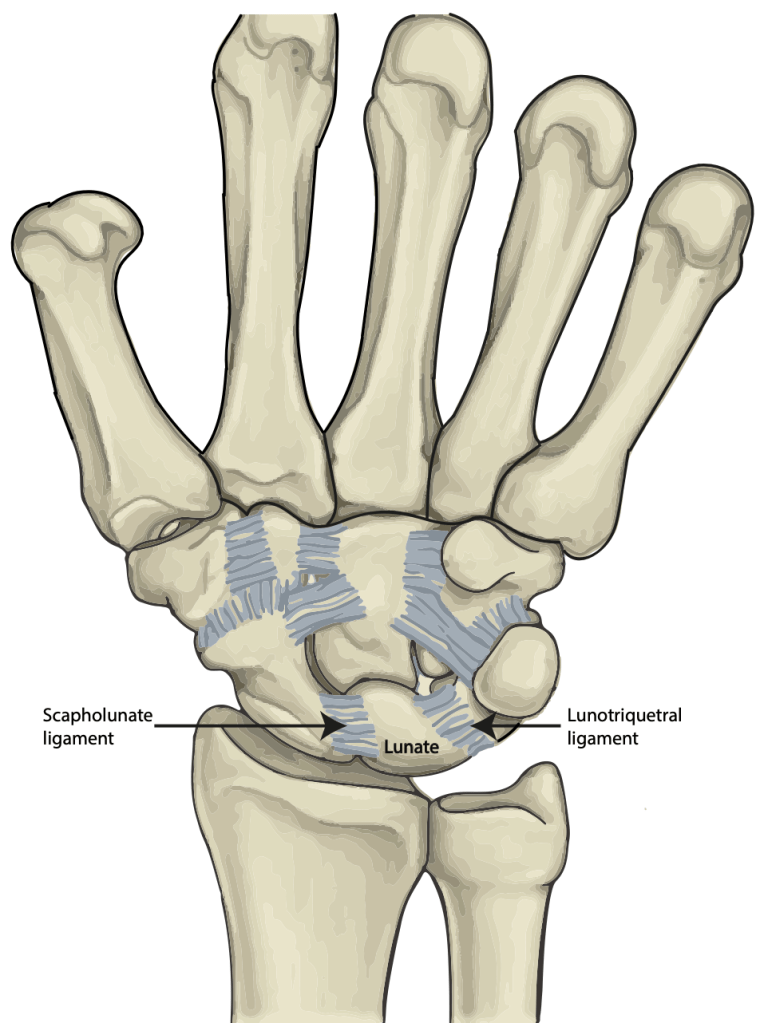

The lunate bone sits in the middle of a row of 3 bones, and is very firmly bound to the bones on either side by the scapholunate and lunotriquetral ligaments. These ligaments are short but very strong. They bind the lunate bone in its pivotal role at the centre of the wrist.

The bones of the wrist can be seen on the X-ray below: